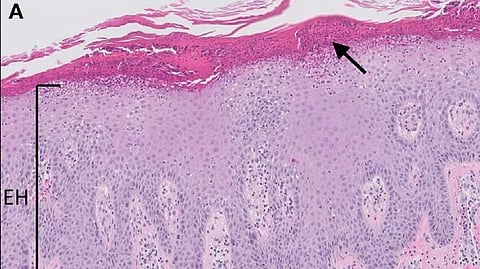

The clinical picture of psoriasis can vary from minor distress in an individual to causing severe damage to the quality of life. It is a long-standing condition that includes an asymptomatic period followed by symptomatic periods. The skin forms red patches and scales that can be white or silvery or grey and are most commonly found on elbows, knees, back, scalp and nails. It can be itchy and can form painful fissures and cracks that can cause bleeding and disable the person. Psoriasis can affect the joints known as psoriatic arthritis, which is characterized by swelling, stiffness, and pain in multiple joints, especially in the morning.